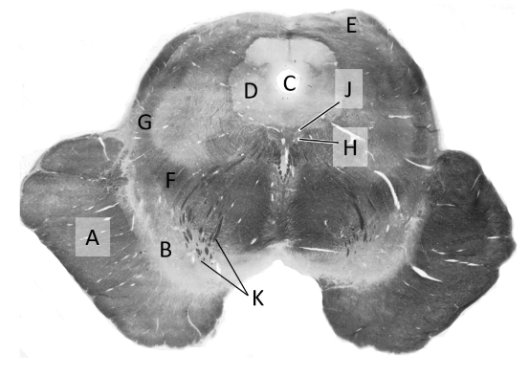

at what level is this?

mid midbrain

what is a?

basis pedunculi/ cerebral peduncle

what is b?

substantia nigra

what is c?

cerebral aqueduct

what is d?

periaqueductal gray

what is e?

superior colliculus

what is f?

medial lemniscus (mb)

what is g?

spinothalamic tract

what is h?

oculomotor nucleus

what is j?

edinger-westphal nucleus

what is k?

oculo-motor nerve fibres